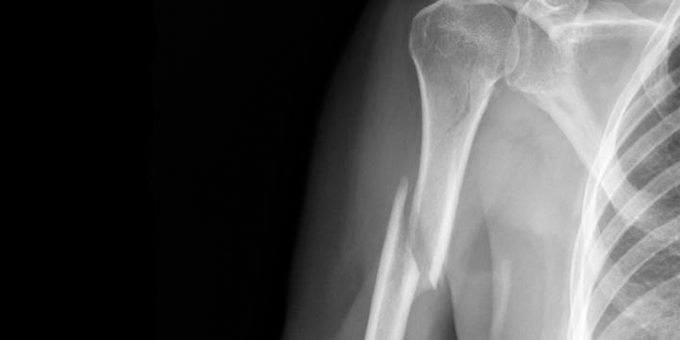

Справедливость этого предположения решили проверить американские ученые. В ходе эксперимента часть пациентов, столкнувшихся с переломами костей и растяжениями, получали обычные безрецептурные анальгетики, а остальные принимали значительно более мощные опиоидные препараты.

Оказалось, что в деле уменьшения уровня боли никакой существенной разницы между этими двумя классами лекарств не существует, по крайней мере когда вопрос касался краткосрочной и сильной боли. Вполне возможно, что результаты этого эксперимента изменят отношение врачей к использованию мощных лекарств, в перспективе вызывающих зависимость.